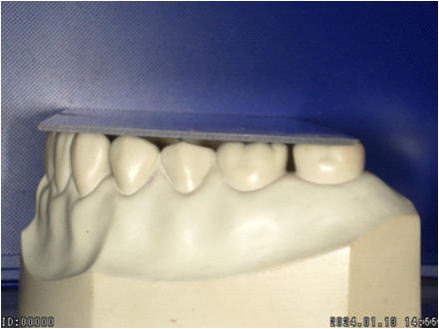

【正常な咬合関係】 |

正常な噛み合わせは、正中が合っており、左右ほぼ対称です。

前後の噛み合わせも平面的であるため、ズレることなくしっかり咬むことが出来るわけです。 |